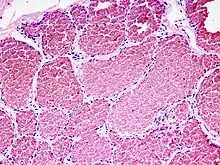

![]() Kapilläres Hämangiom der Haut, Hautbiopsie, H&E. |

![]() idem, stärkere Vergrößerung |